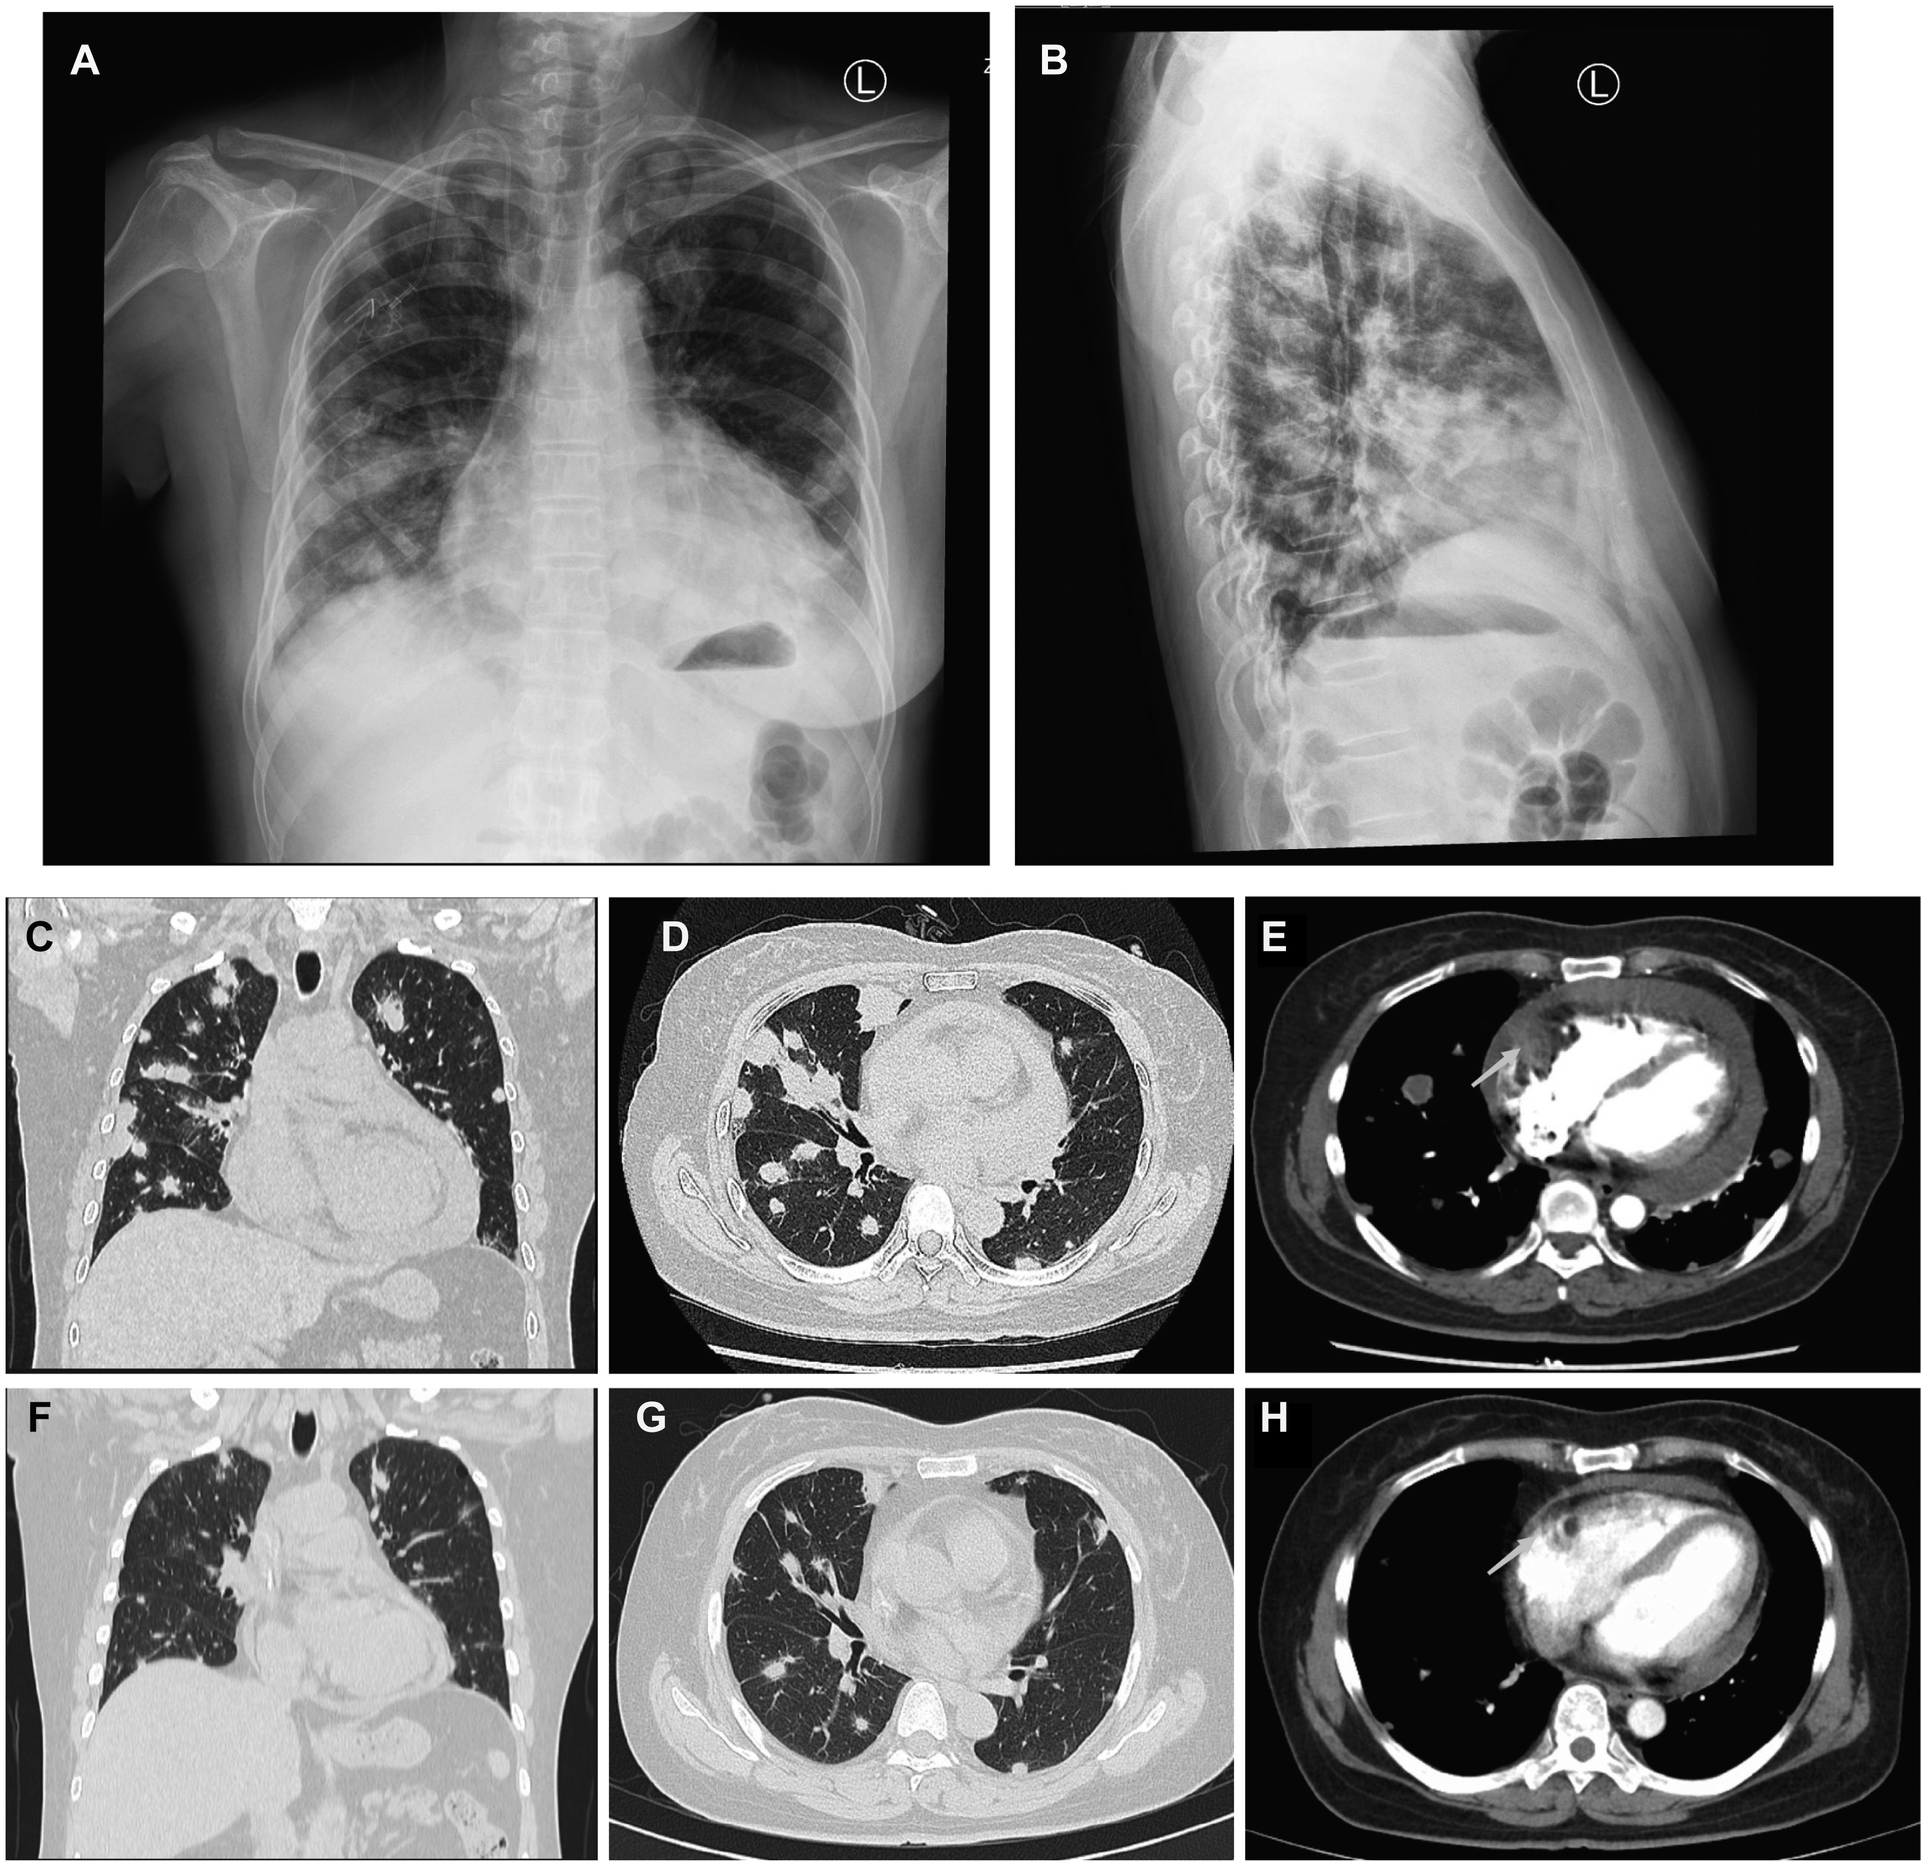

A 50-year-old woman, who had been experiencing shortness of breath and chest tightness for four months, was admitted to a nearby hospital. A chest computed tomography (CT) revealed enlarged heart with pericardial effusion as well as multiple lesions in lungs with suspected infection. CT-guided needle biopsy of pulmonary lesions was performed. Only heterozygous cells were found in the necrosis, and the pathological findings of the lung biopsy were unremarkable. After a few days, the patient gradually felt dyspnea and weakness. She was transferred to our cardiology department for a conclusive diagnosis. Blood testing showed high level of the C-reactive protein (CRP) (16.6 mg/L), pro-Brain natriuretic peptide level of 224 pg/mL, D-dimer of 2050 ug/L, and tumor marker CA125 (60.1 U/ml). Her chest x-ray (Figures 3A,B) and chest CT (Figures 3C,D) revealed multiple lung lesions. Enhanced chest CT showed an oval hypodense contrast filling defect in the right atrium wall. The size is about 55mm × 28mm × 36 mm (Figure 3E). Transthoracic echocardiography (Figure 4A) and contrast-enhanced Cardiac magnetic resonance (CMR) imaging (Figure 4B) confirmed a large irregular mass (55.2 × 38.1 × 33.9 mm) in the right atrium (RA) invading the superior vena cava. We suspected that this was a cardiac malignant tumor with extensive lung metastases, and then performed an ICE-guided right atrial biopsy (Figures 4C,D, Supplementary Appendix Videos S3-4). Histopathological results (Figure 4E) confirmed the diagnosis of cardiac angiosarcoma, with spindle tumor cells staining positively for CD34, CD31, Fli-1, and ERG, with ki-67 proliferation index reached 60%. After being transferred to the oncology unit, this patient was advised to undergo chemotherapy and targeted therapy without having a mass removed. The patient was treated with chemotherapy (Paclitaxel 207 mg/m2 day1, liposomal doxorubicin 30 mg/m2 day1, and Anlotinib day1–14 for targeted therapy). After 5 courses of chemotherapy, the lateral wall of the right atrium has no occupied, and the number of lung metastases was less than before (Figures 3F–H).

Figure 3

Comparison of lung metastases and cardiac mass before and after chemotherapy of Case2. (A,B) Frontal and lateral Chest x-ray demonstrated extensive pulmonary lesions. (C) Chest CT at coronal view and (D) axial view revealed severe lung metastases. (E) Contrast-enhanced Chest CT reveals a mass lesion (arrow) along the superior and posterior right atrial wall without enhancement. After 5 courses of chemotherapy, the number of lung metastases (F,G) was less than before (C,D), and the lateral wall of the RA (H) has no occupied (arrow) compared to earlier (E).